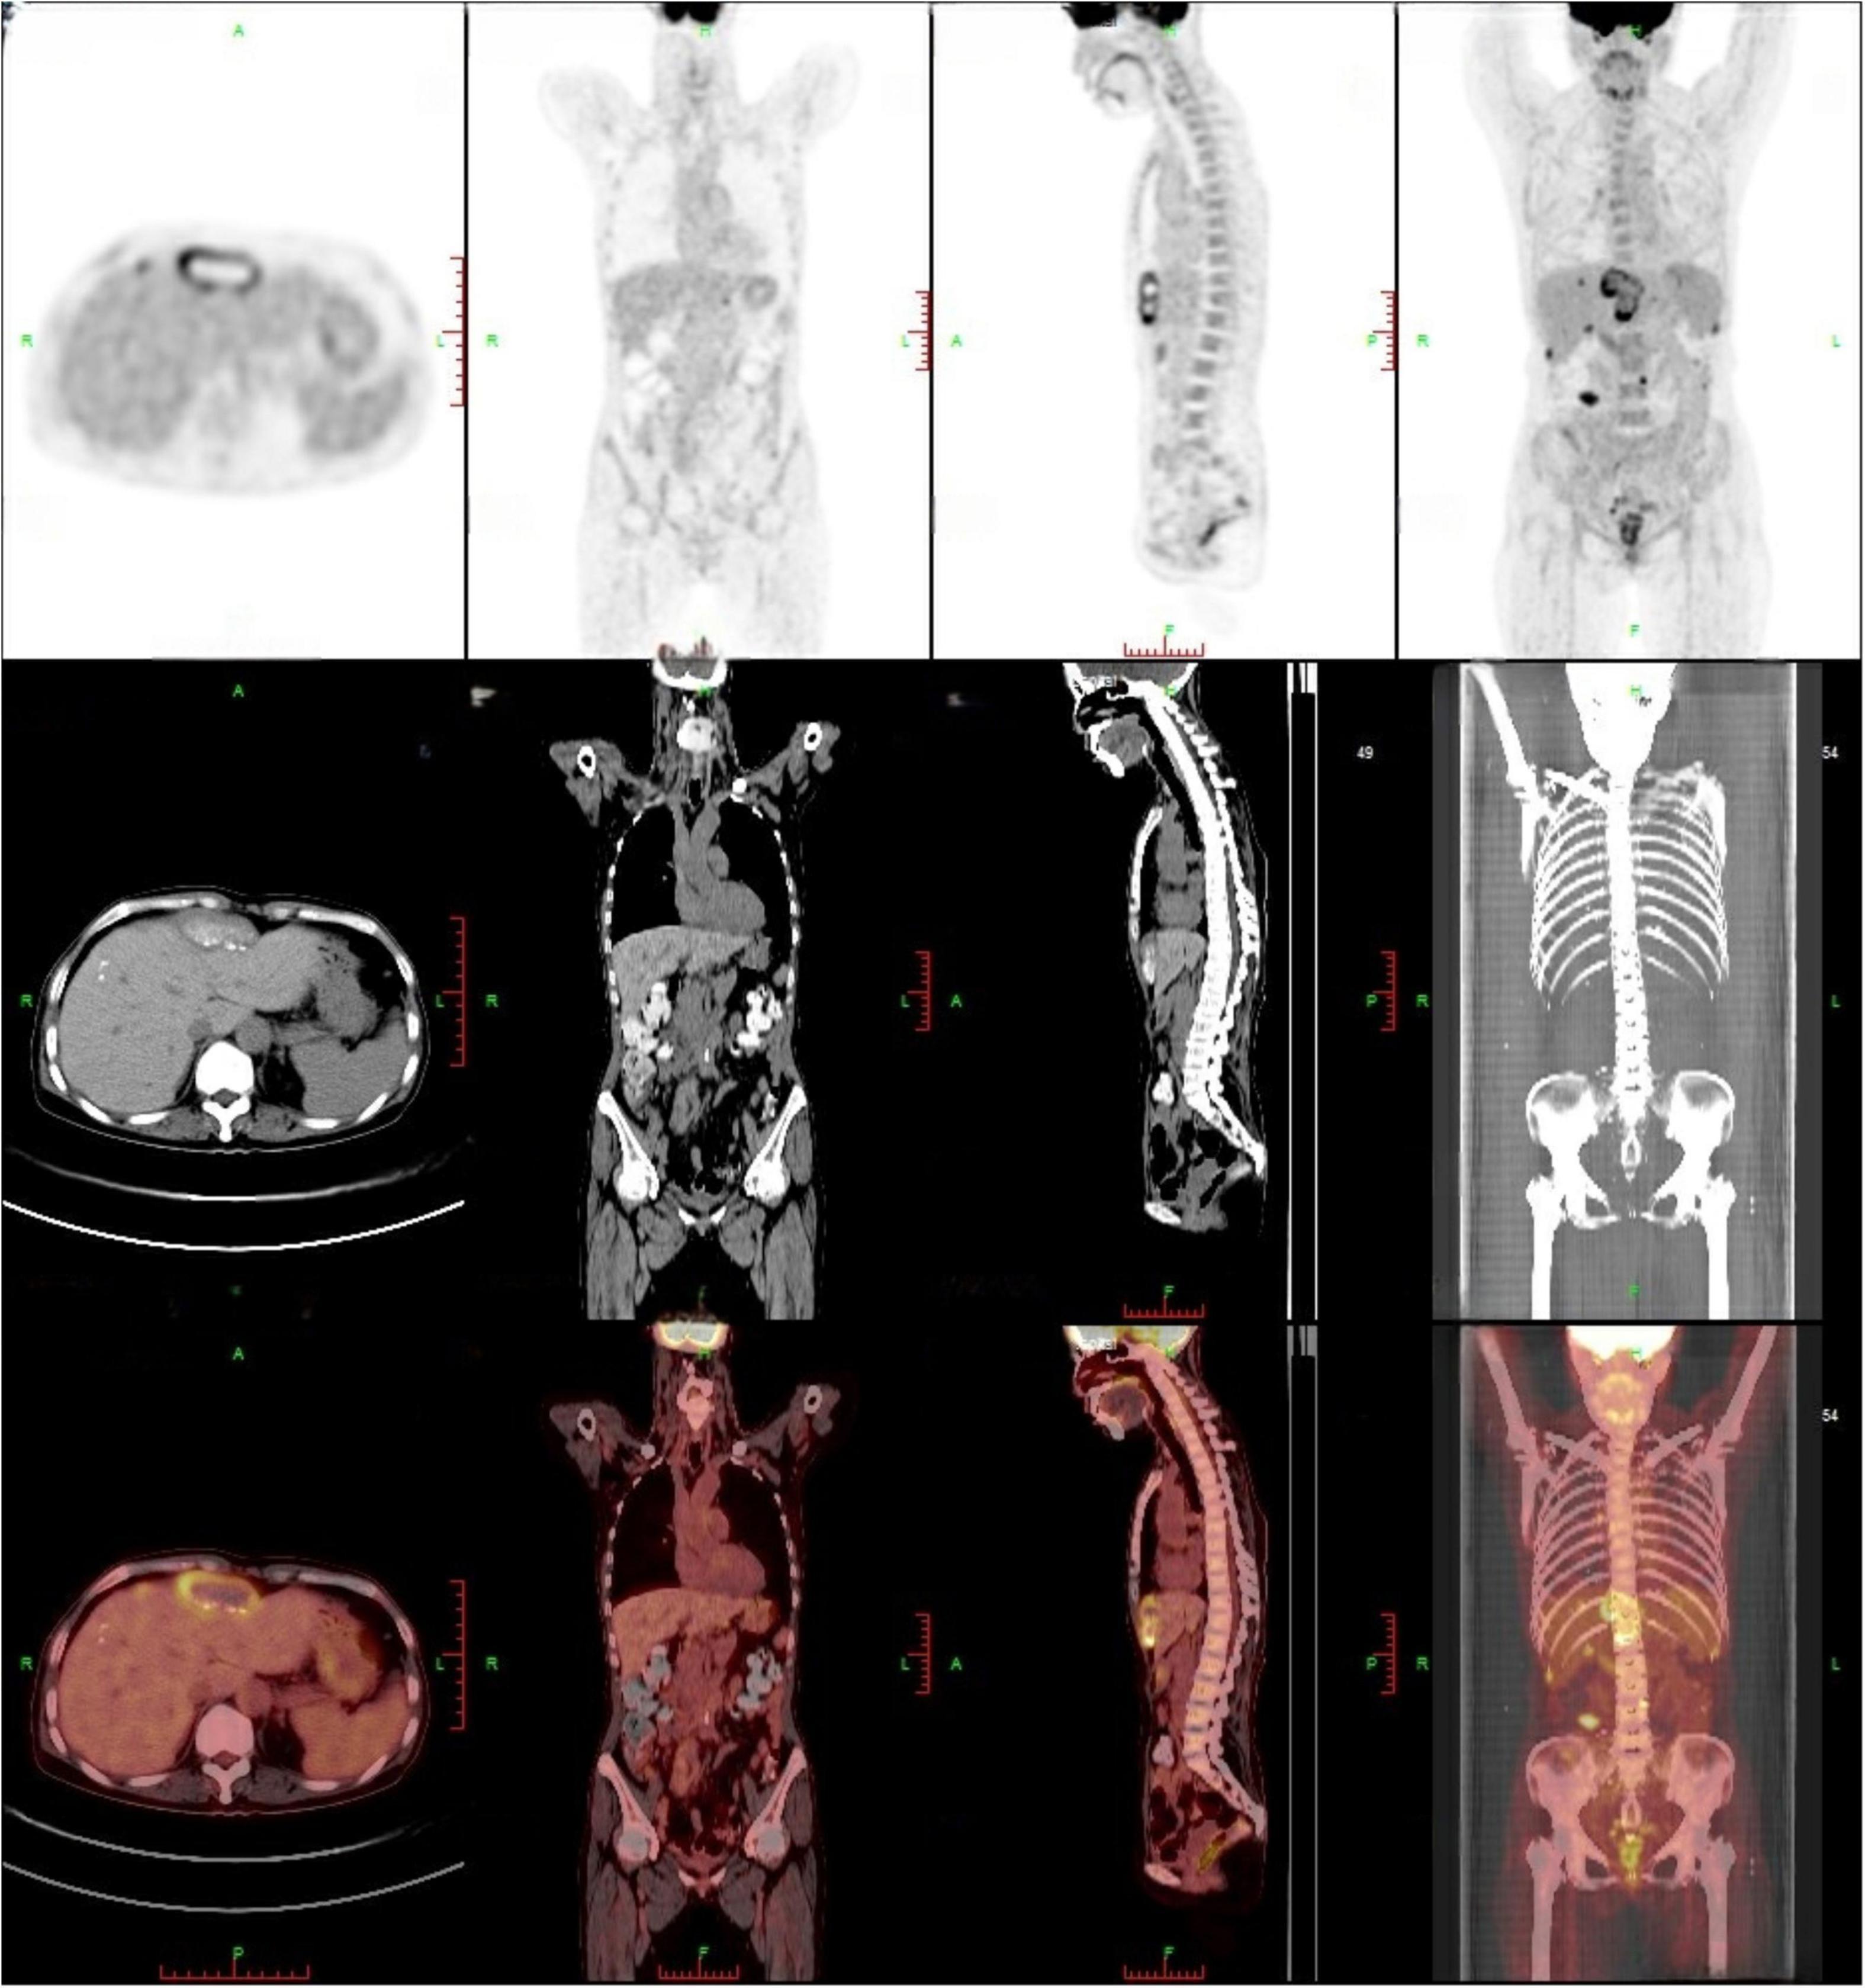

Contrast-enhanced abdominal CT (Figure 1) revealed an irregular soft-tissue density lesion (approximately 5.2 × 2.3 × 6.2 cm) anterior to the liver, accompanied by a 1.5 cm nodule in the left peritoneal cavity, raising suspicion of malignancy. Subsequent PET-CT (Figure 2) confirmed multiple FDG-avid peritoneal nodules and masses, with a maximum standardized uptake value (SUV∼max∼) of 7.1, further supporting the suspicion of metastatic disease. Blood and urine cultures showed no growth.

FIGURE 2

PET-CT findings: multiple peritoneal nodules and masses (approximately 5.5 × 2.2 cm) exhibited increased FDG accumulation, with a maximum SUV of 7.1, suggesting peritoneal metastasis. A high-uptake lesion beneath the right abdominal wall was recommended for percutaneous biopsy.

In this case, the initial whole-abdomen enhanced CT scan revealed a hepatic anterior mass and multiple intra-abdominal nodules. Subsequent PET-CT demonstrated multiple FDG-avid lesions in the peritoneum, with a maximum standardized uptake value (SUVmax) of 7.1. These imaging features closely mimicked malignant neoplasms, particularly peritoneal metastases. Literature suggests that 18F-FDG PET/CT can detect focal hypermetabolism on cardiac valves or vascular walls, facilitating diagnosis of infectious endocarditis and vascular infections in chronic Q fever (15). This modality improves diagnostic accuracy when incorporated into the Duke criteria and helps localize sites of chronic Q fever infection (16, 17). In the present case, however, PET-CT demonstrated increased metabolic activity initially suggestive of multifocal metastatic malignancy rather than Q fever. Subsequent percutaneous biopsy revealed only basophilic amorphous material and granulomatous inflammation with negative acid-fast staining. These non-specific findings provided no definitive microbiological evidence and led to the initial misdiagnosis of tuberculous peritonitis.